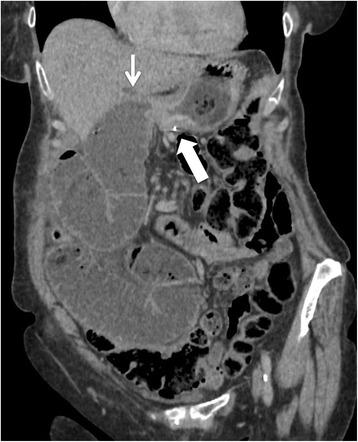

Two patients developed gastric stump carcinoma 19 and 10 years after pancreaticoduodenectomy for malignant ampulloma and total pancreaticoduodenectomy for pancreatic adenocarcinoma, respectively. Both patients had pT4 signet-ring cell carcinoma involving the gastrojejunostomy site that was revealed by bleeding or obstruction. Patient 1 is alive and remains disease-free 36 months after completion gastrectomy. Patient 2 presented with peritoneal carcinomatosis and died after palliative surgery. We identified only 3 others cases in the English literature.

Prolonged biliary reflux might be the most important risk factor of gastric stump carcinoma following pancreaticoduodenectomy. Its incidence might increase in the future due to prolonged survival observed after pancreaticoduodenectomy for benign and premalignant lesions.